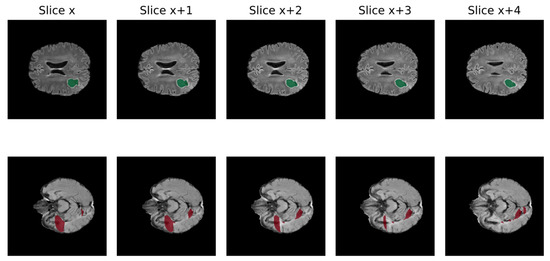

- Reina, G.A.; Panchumarthy, R.; Thakur, S.P.; Bastidas, A.; Bakas, S. Systematic Evaluation of Image Tiling Adverse Effects on Deep Learning Semantic Segmentation. Front. Neurosci. 2020, 14, 65. [Google Scholar] [CrossRef]

- Huang, B.; Reichman, D.; Collins, L.M.; Bradbury, K.; Malof, J.M. Tiling and Stitching Segmentation Output for Remote Sensing: Basic Challenges and Recommendations. arXiv 2018, arXiv:1805.12219. [Google Scholar] [CrossRef]